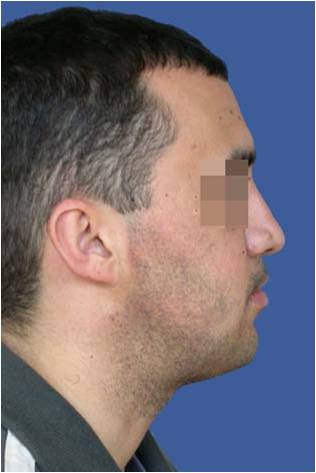

Пациент с преразвитие на долната челюст (мандибуларен прогнатизъм) – преди и след реконструкция на долната челюст - случай на доц. Джоров.

Пациенти с недостатъчност в развитието на долната челюсти брадата (мандибуларна микрогнатия с микрогения) преди и след реконструкции на долната челюст и брадата - случаи на доц. Джоров.

Пациент с асиметрично преразвитие на долната челюст (асиметричен мандибуларен прогнатизъм) – преди и след реконструкция на долната челюсти нивелиране на брадата- случай на доц. Джоров

Пациент с недостатъчност в развитието на горната челюст (сагитална максиларна недостатъчност) – преди и след реконструкция на горната челюст - случай на доц. Джоров

Пациенти с недостатъчност в развитието на горната челюст и преразвитие на долната – преди и след едновременна реконструкции на горната, долната челюст и брадата - случаи на доц. Джоров